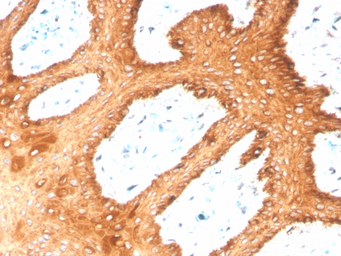

IHC-P analysis of human skin tissue section using GTX02665 Cytokeratin 2 antibody [KRTH/4392R].

IHC-P analysis of human skin tissue section using GTX02665 Cytokeratin 2 antibody [KRTH/4392R].